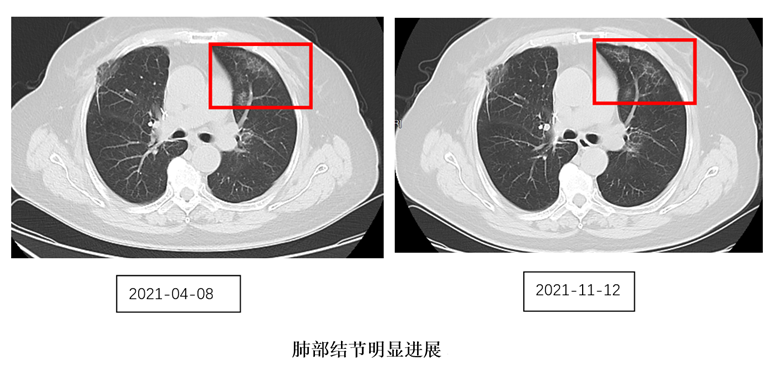

双肺磨玻璃结节多年 多次检查病因未明

2017年10月,来自苏州的陈阿姨因肺癌行胸腔镜下右肺上叶切除术。两年后,患者出现活动后胸闷的症状,外院肺部CT提示双肺出现多发磨玻璃影。多科评估后,制定了抗感染后定期复查的方案。在后续一年的随访中,病灶没有明显变化。但在今年的3月,双肺的结节明显增多了。患者完善了PET-CT检查,也先后经历2次气管镜检查,但都没有明确病因。综合考虑后,决定继续抗感染治疗两个月。两个月后,复查发现病灶还是在进展。如此一来,后续治疗该如何开展成了个问题:继续行抗感染治疗?再次行气管镜治疗?行外科手术或者重新开始化疗或靶向治疗?